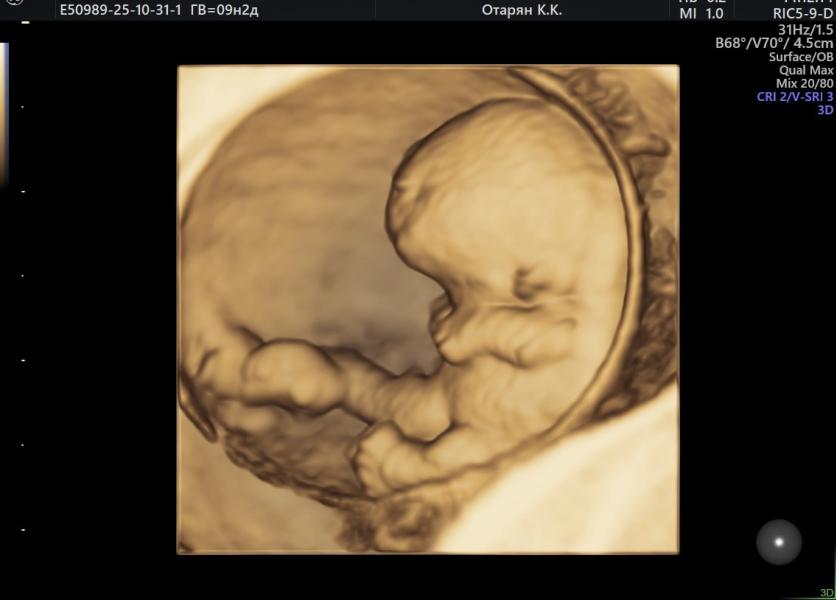

9 недель и 2 дня

А тут.уже целый человечек с ручками и ножками. Я в шоке, какие изменения за 2 недели. 2,3 см и чсс 179. Растем❤️